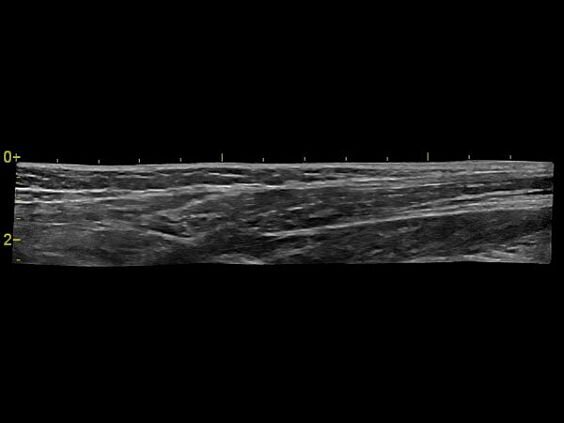

- B-Flow — недопплеровская визуализация кровотока в сосудах с улучшенными характеристиками пространственного и временного разрешения, дает возможность оценить кровоток и структуру сосудистых стенок без ограничений свойственных доплеровской методике.

- LOGIQview — технология панорамного сканирования, позволяющая визуализировать крупные анатомические объекты в рамках одного изображения.